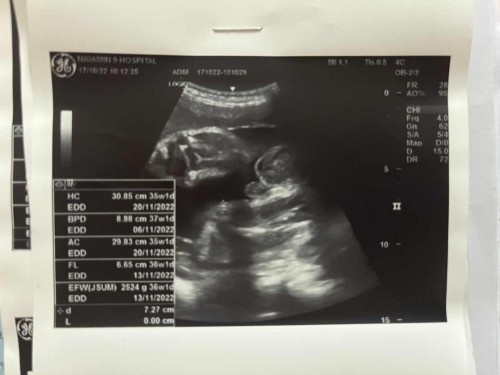

ทำไม ในภาพอายุครรภ์ 36สัปดาห์ แต่หมอเขียนในสมุดชมพู 33สัปดาห์ แล้วกำหนดคลอดเราจริงๆ วันไหนกันนะ งง ไปหมด

กำหนดคลอดจะอยู่ในสมุดสีชมพู โดยจะยึดจากการฝากท้องตอนแรกเป็นหลักค่ะ ส่วนในรูปอัลตราซาวจะเป็นขนาดน้ำหนักปัจจุบันว่าลูกโตเกินเกณฑ์ ตามเกณฑ์ หรือต่ำกว่าเกณฑ์ค่ะ แสดงว่าน้องน้ำหนักดีเกินเกณฑ์

เป็นการวัดขนาดประมาณอายุครรภ์ค่ะ กำหนดคลอดคือที่เค้านับ ตั้งแต่แรก